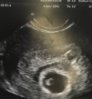

Dziewczyny przepraszam ale pol godz opoznilo sie bija dwa serduszka jedno slabiej sie rozwija za dwa tyg kolejne usg

Napisze z domu musze dojsc do siebie

• image.jpeg

image.jpeg

604,5 KB · Wyświetleń: 106